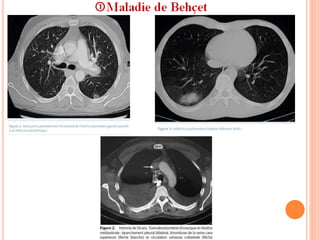

6- Manifestations pulmonaires: 10%

 EP, thrombose pariétale, et anévrysmes artériels ++ , parfois

aussi des infiltrats avec ou sans pleurésie.

 Cliniquement: dyspnée, douleurs thoraciques et surtout

hémoptysies.

 Imagerie: Hémorragies et infarctus.

Anévrysmes artériels.

Pneumonie organisée.

Syndrome de Hughes-Stovin